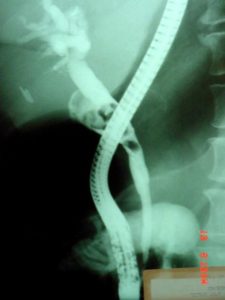

Жовчний міхур може бути видалений лапароскопічно і відкритим шляхом. У першому випадку інструменти вводяться в черевну порожнину через мікро розрізи. Малоінвазивна операція, зменшується кількість ускладнень і днів лікування у стаціонарі. Відновлення займає менше часу. Рубці практично не помітні. Косметичний ефект особливо важливий, так як найбільш часто патологія зустрічається у жінок. У багатьох клініках світу 95-97% пацієнтів оперуються лапароскопічно.

Відкрита операція з видалення жовчного міхура з розрізом по передній черевній стінці виконується при виявленні захворювань, не розпізнаних до холецистектомії (злоякісні та доброякісні пухлини в жовчному міхурі, шлунку або в ободовій кишці) або ускладнень (масивна кровотеча, яку неможливо зупинити лапароскопічно, пошкодження позапечінкових жовчних проток).